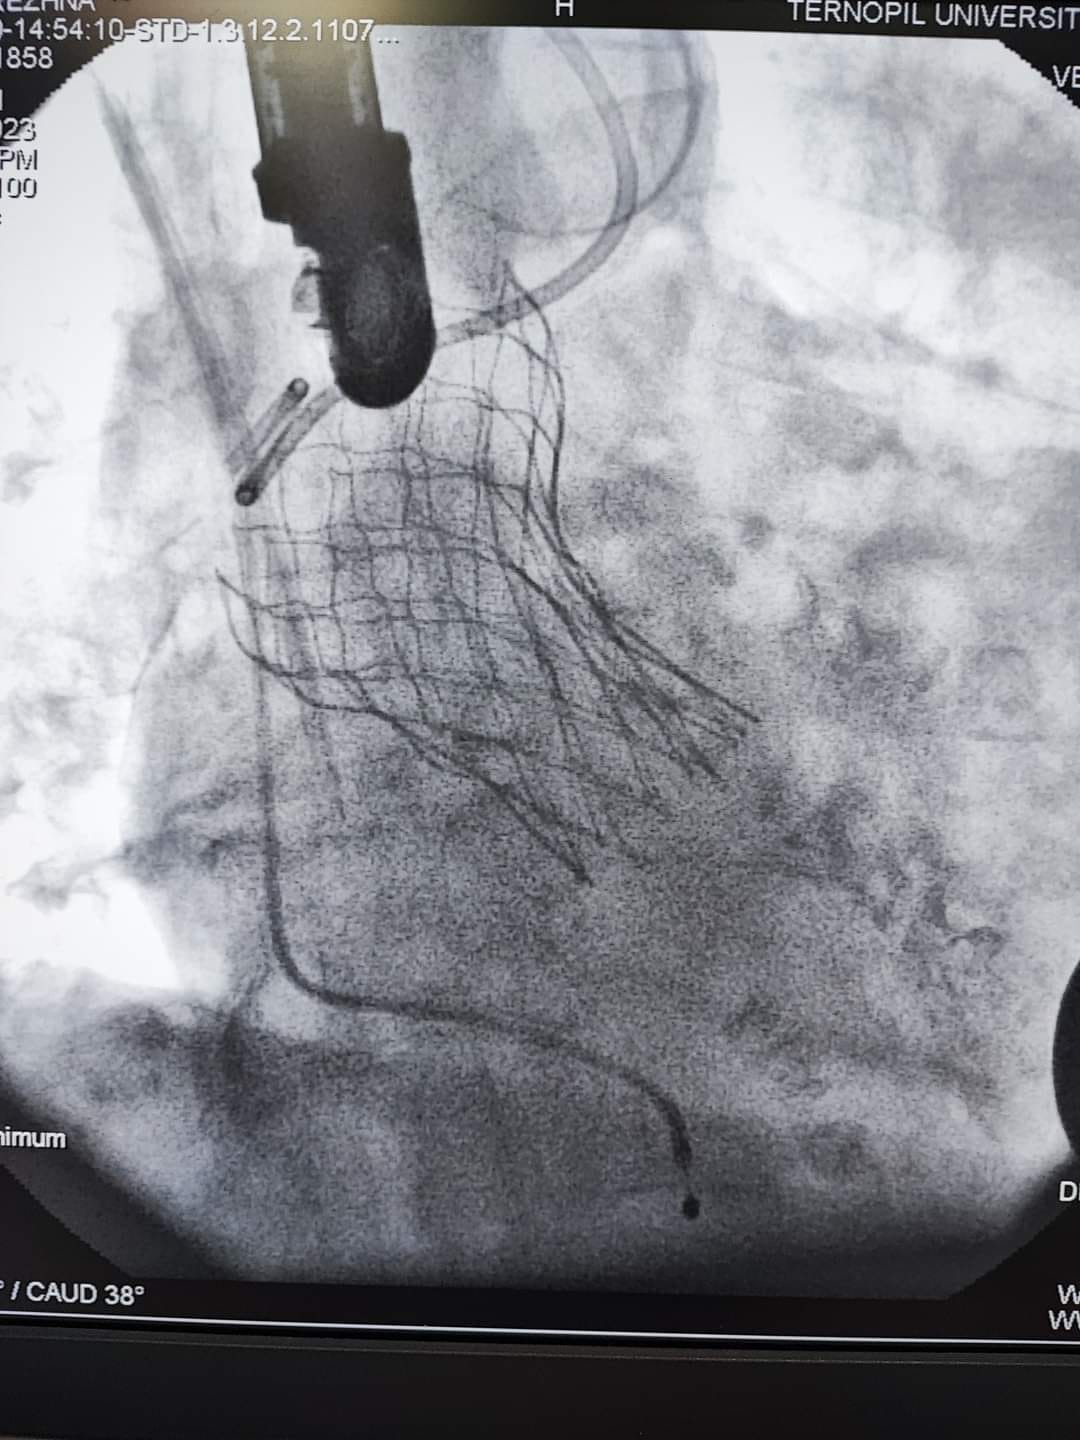

«Одна з них має важке викривлення хребта, внаслідок якого анатомічно складне положення серця, аорти та інших внутрішніх органів. Це практично унеможливлювало виконання заміни клапана іншим доступом окрім трансапікального, що, власне, було й проведено. Суть операції полягає в тому, що на працюючому серці виконується невеликий отвір, на якому через трубку-катетер по провіднику вводиться згорнутий клапан. Позиціонування контролюється як рентгенівським зображенням, так і черезстравохідним ультразвуковим датчиком. Після імплантації хірург затягує вузол навколо отвору і вшиває рану. Крововтрата є мінімальною», – наголосив Богдан Маслій.